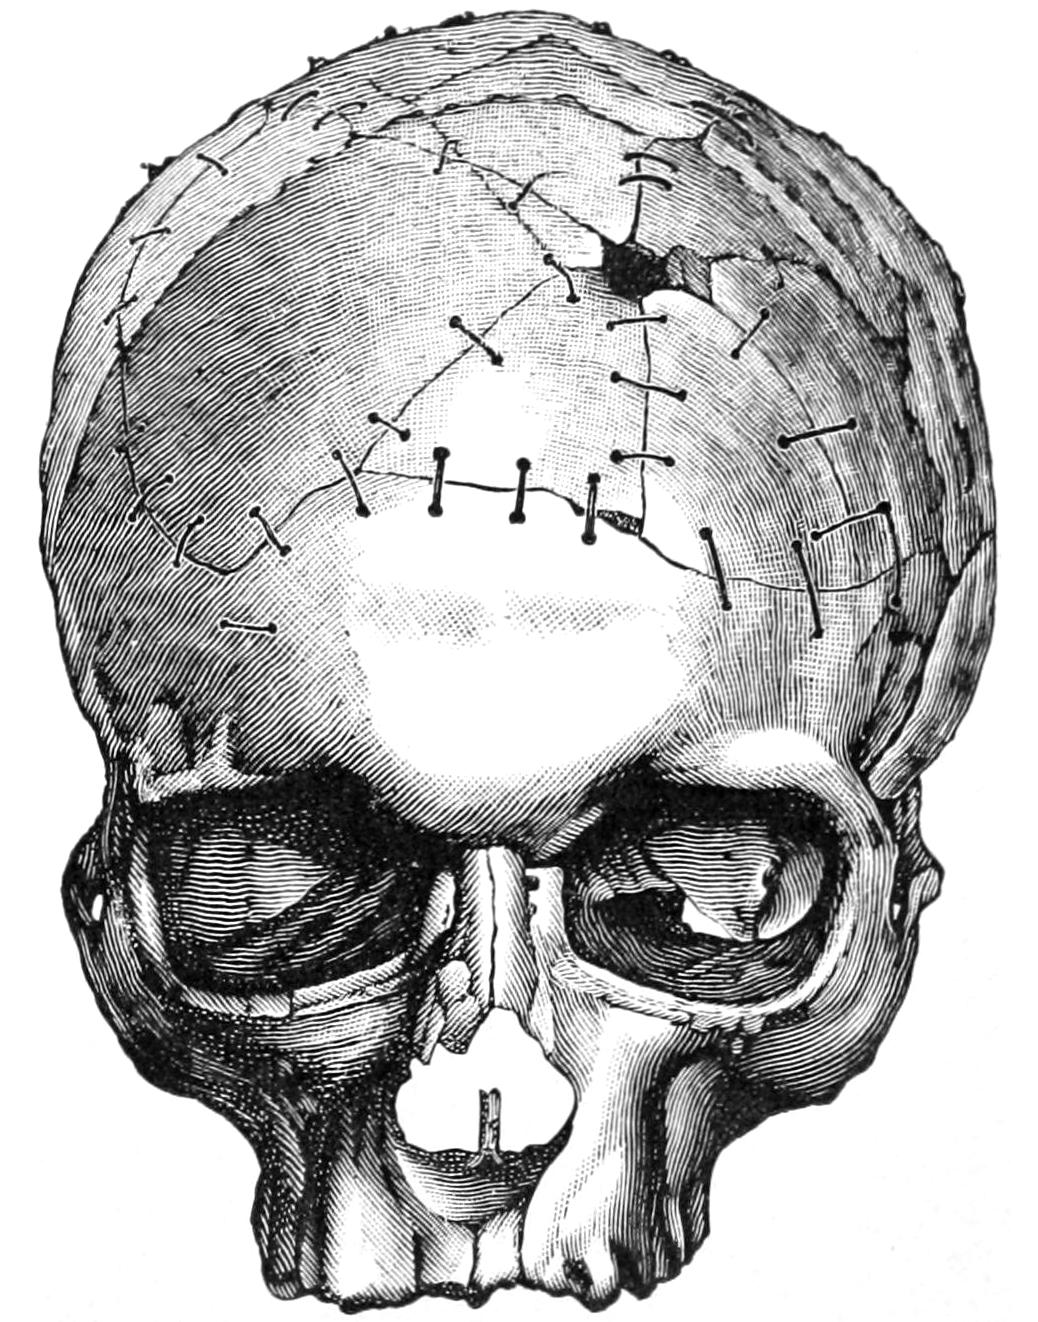

INJURIES AND SURGICAL DISEASES OF THE HEAD 545

CHAPTER XXXVII.